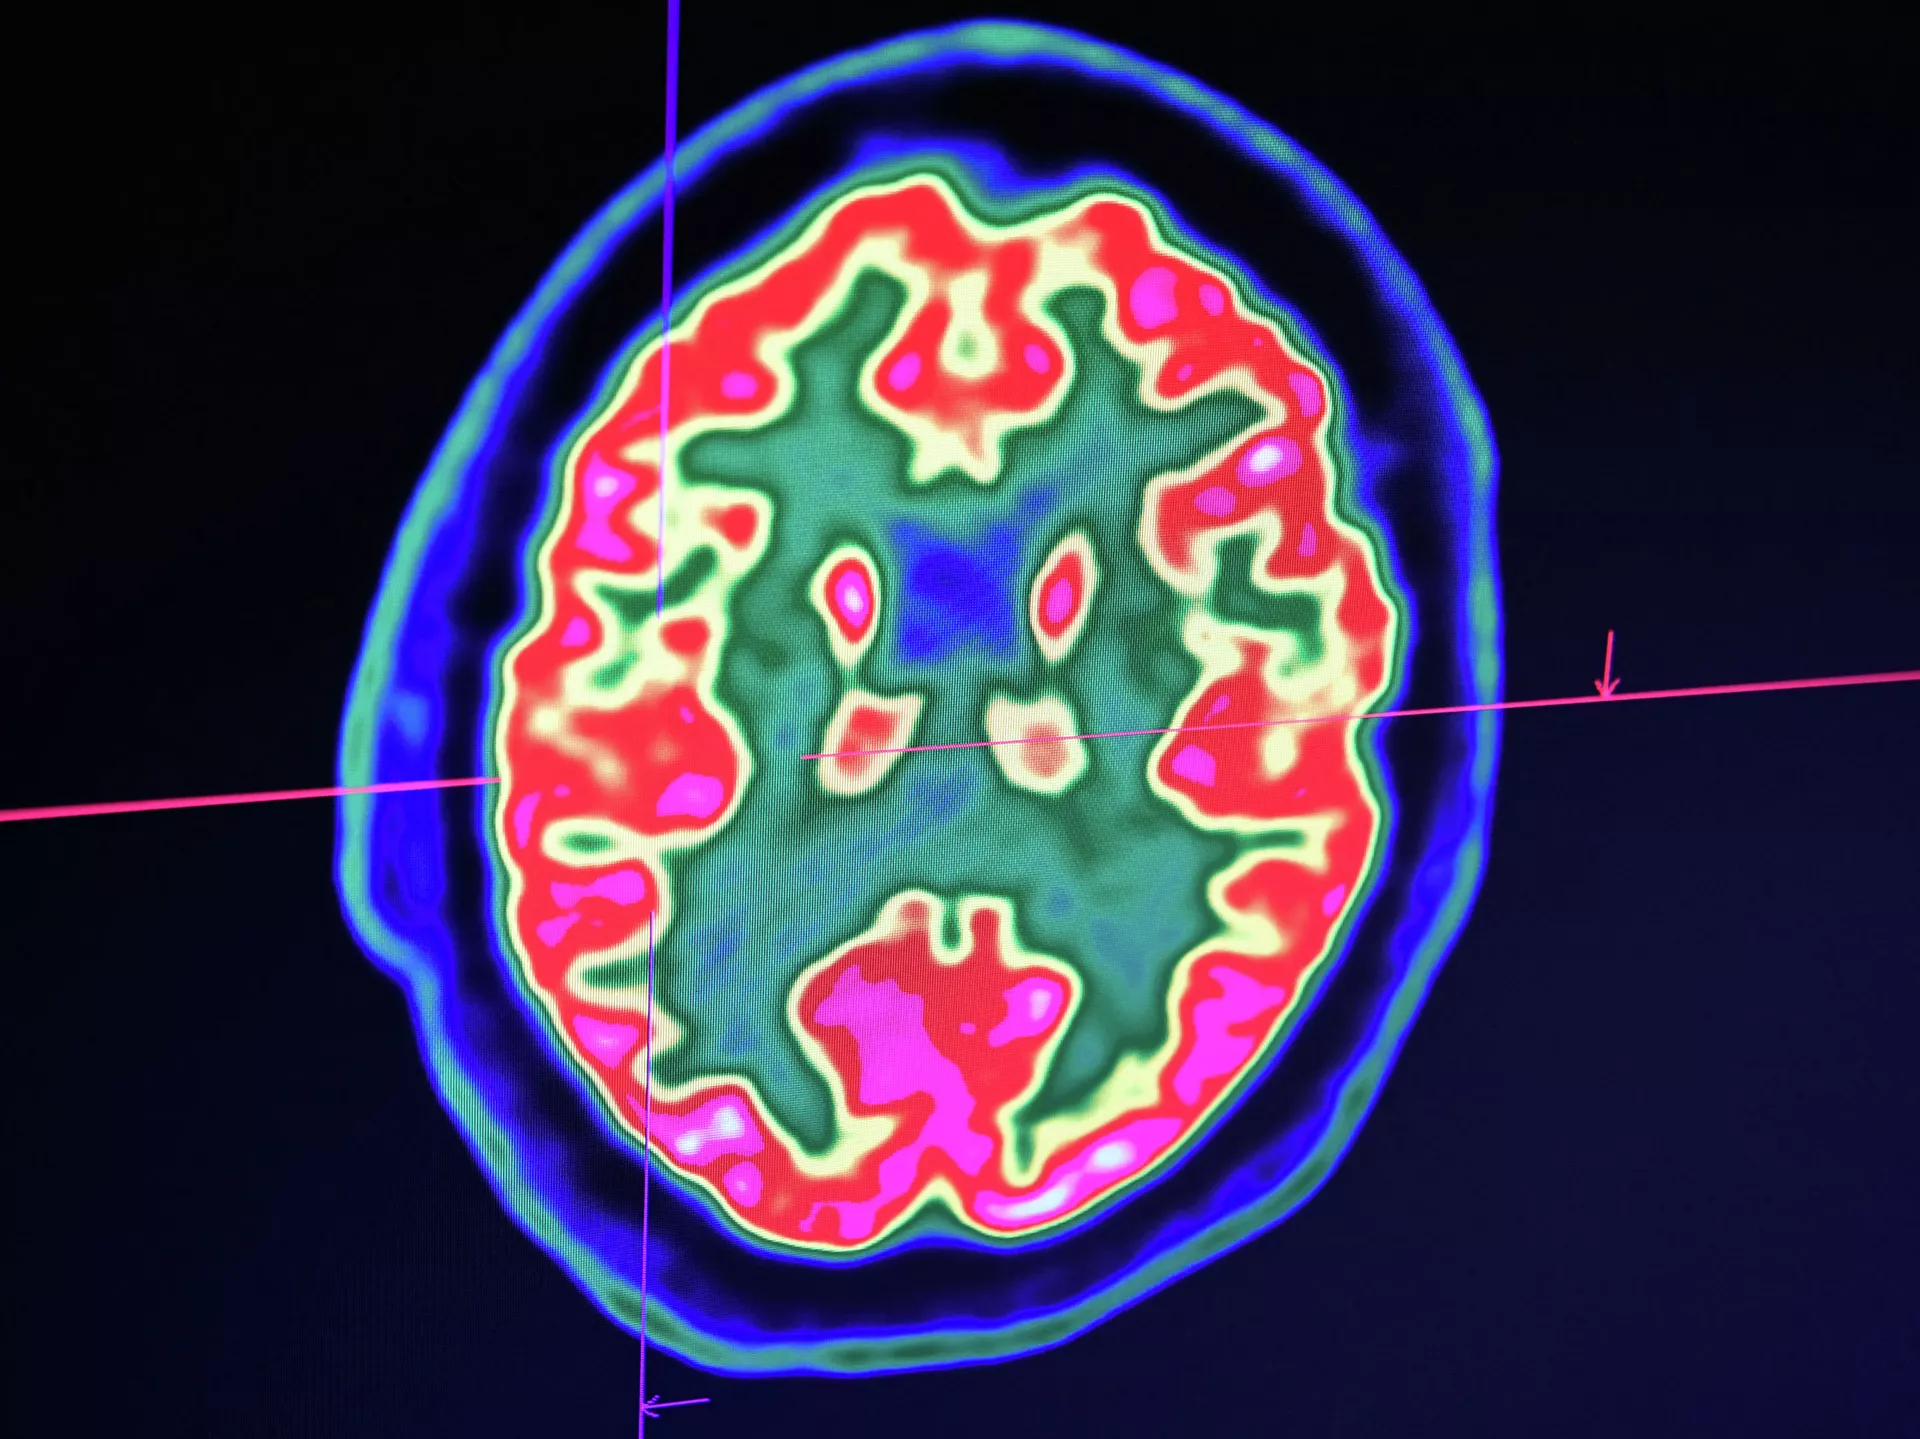

БИШКЕК, 12 фев — Sputnik. Как восстановить работоспособность мозга после COVID-19, телеканалу "Мир 24" рассказал невролог Василий Грибанов.

Он отметил, что при любой форме коронавирусной инфекции страдает нервная система. Ориентировочный срок восстановления после заболевания — три-шесть месяцев.